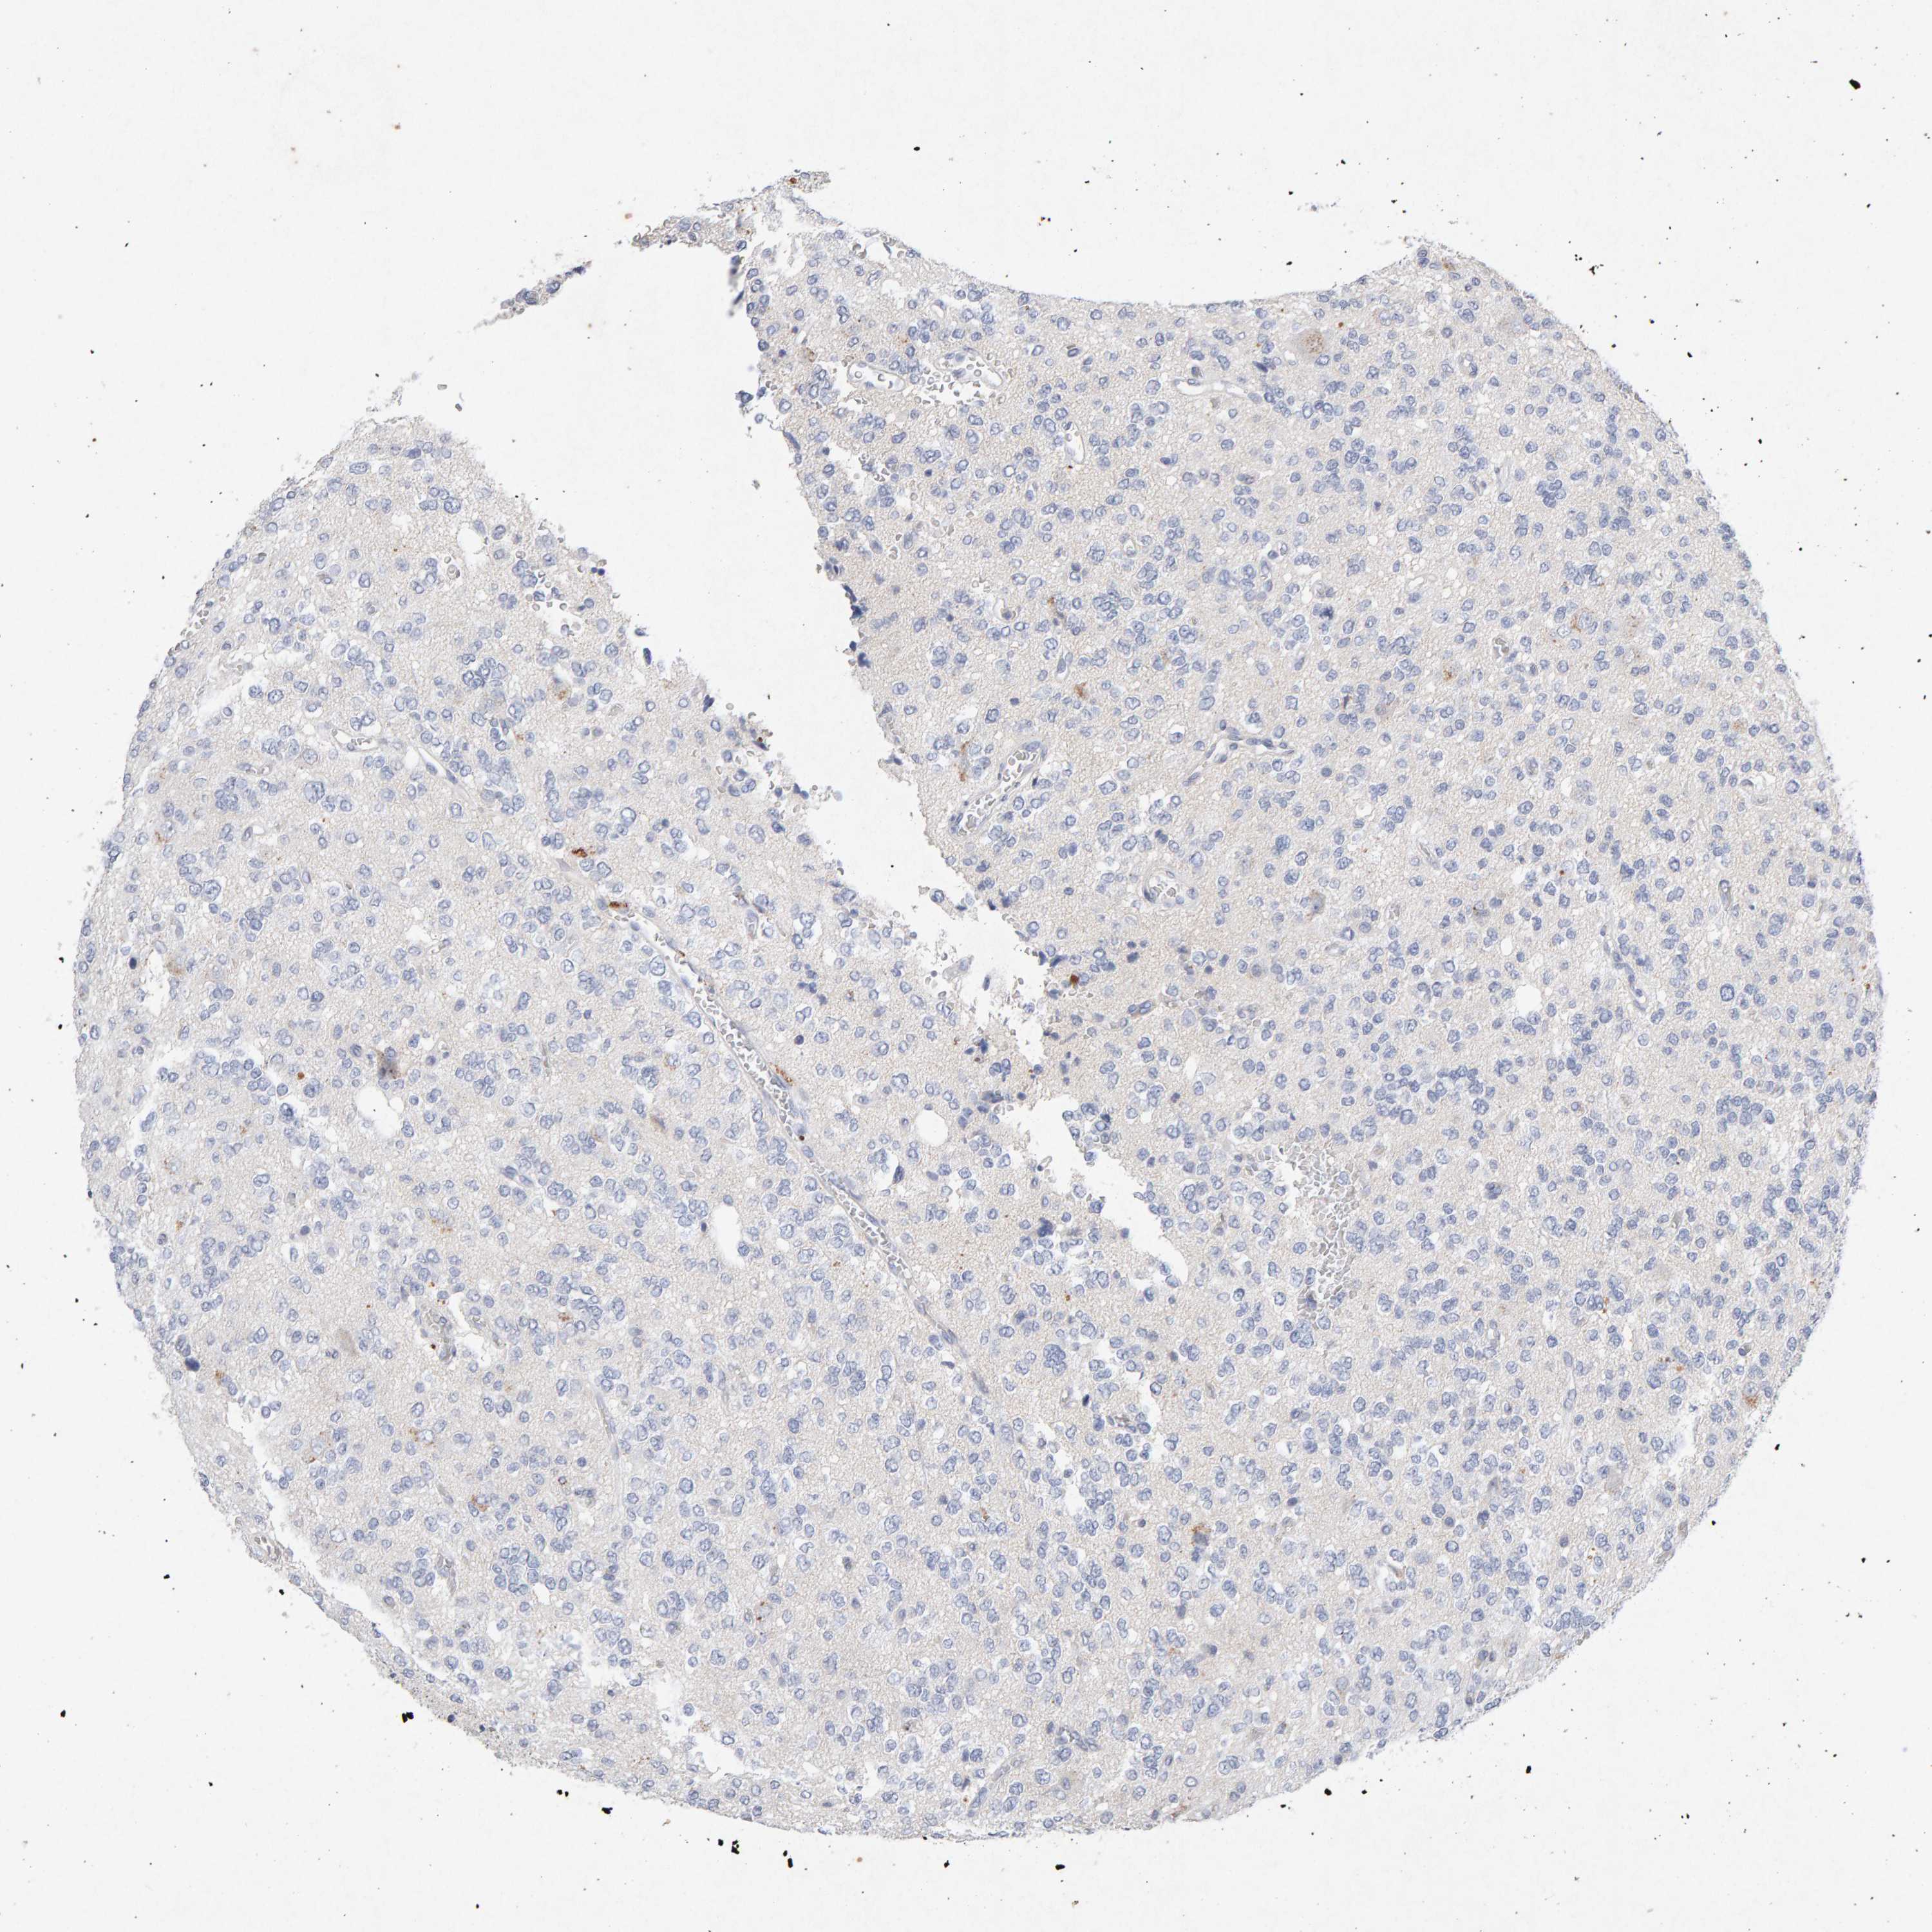

GLIOMA - Protein expressioni

A mouse-over function shows sample information and annotation data. Click on an image to view it in a full screen mode. Samples can be filtered based on level of antibody staining by selecting one or several of the following categories: high, medium, low and not detected. The assay and annotation is described here.

Note that samples used for immunohistochemistry by the Human Protein Atlas do not correspond to samples in the TCGA dataset.

Antibody stainingi

Antibody staining in the annotated cell types in the current human tissue is reported as not detected, low, medium, or high, based on conventional immunohistochemistry profiling in selected tissues. This score is based on the combination of the staining intensity and fraction of stained cells.

Each image is clickable and will lead to virtual microscopy that enables deeper exploration of all samples and also displays staining intensity scores, fraction scores and subcellular localization as well as patient and tissue information for each sample.

Antibody CAB022442

Antibody CAB022443

Staining

High

Medium

Low

Not detected

Intensity

Strong

Moderate

Weak

Negative

Quantity

>75%

75%-25%

<25%

None

Location

Nuclear

Cytoplasmic/membranous

Cytoplasmic/membranous,nuclear

Glioma, malignant, High grade

Glioma, malignant, Low grade